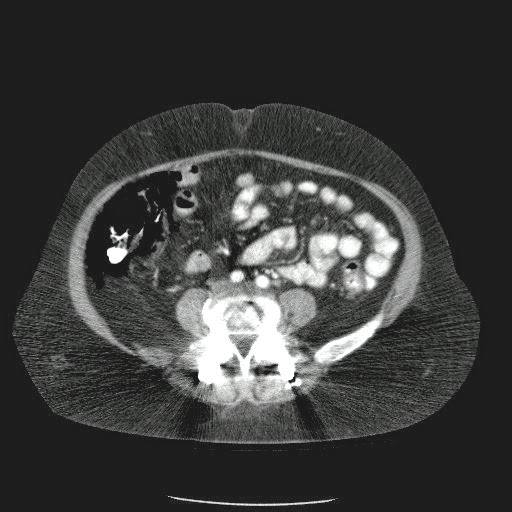

Paciente con antecedente de ALIF (Fusión lumbar intersomática anterior) 360 grados L5-S1 hace siete meses, quién presenta herida de abordaje anterior con dehiscencia de sutura, con cierre por segunda intención, quien consulta por cuadro clínico de dos días de secreción purulenta en herida quirúrgica, niega fiebre, niega otras sintomatología, refiere episodios previos similares.

Paciente en POP de ALIF L5-S1 quien presento dehiscencia de la herida abdominal con ISO superficial ya tratada, sin embargo persiste con dehiscencia y desde ayer con supuración asociado a fiebre subjetiva. Se realiza eco abdominal con colección en pared sugestiva de absceso, elevación de RFA por lo cual se considera se debe hospitalizar para manejo antibiótico, drenaje de la colección, manejo médico y vigilancia neurológica.

- ¿Hallazgos Escanografia?

2. Hay una colección de la pared abdominal en el flanco derecho, que realza en la periferia con el contraste, e intraabdominal tiene aire pero no me parece colección intraabdominal porque la grasa no está alterada.